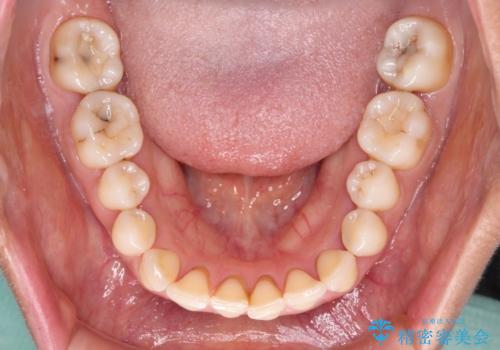

前歯の見た目はもちろん、出血や腫脹のない健全な前歯の状態を獲得することができました。